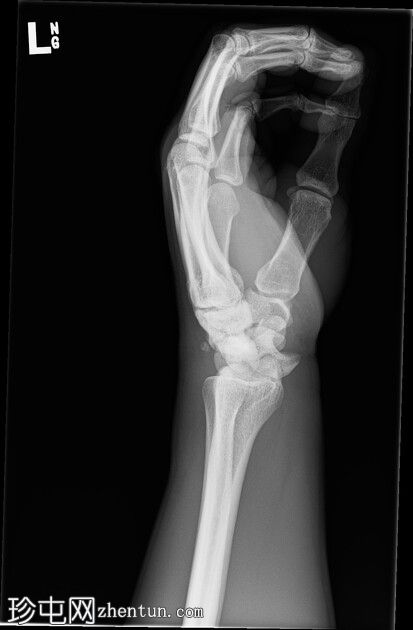

左腕

X光片

正面

斜位

侧面

前后位:舟月骨间隙明显增宽,月骨呈三角形。侧面显示月骨掌侧脱位,头状骨和桡骨远端保持正常排列,符合月骨脱位。陈旧性背侧三角骨骨折。腕部软组织肿胀。